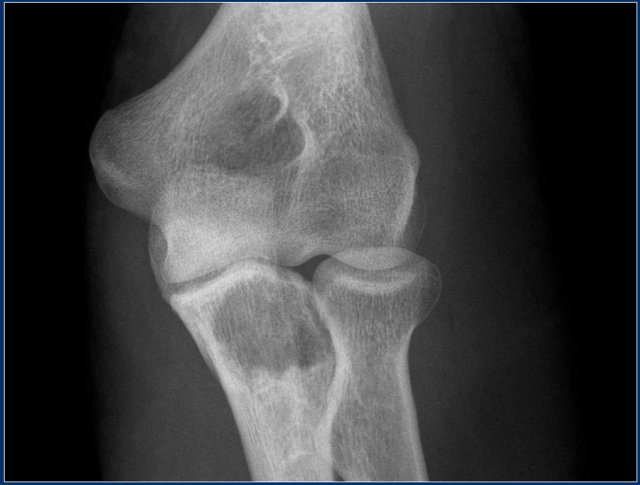

Brown tumor (2)

On the left images of a 30-year-old male with well-defined lytic lesion of the olecranon.

On the radiograph several ridges can be seen and a pathologic fracture (arrow).

The T2-weighted image with fat saturation demonstrates fluid-levels due to sedimentation.

Most likely diagnosis: giant cell tumor and ABC.

Biopsy revealed brown tumor.